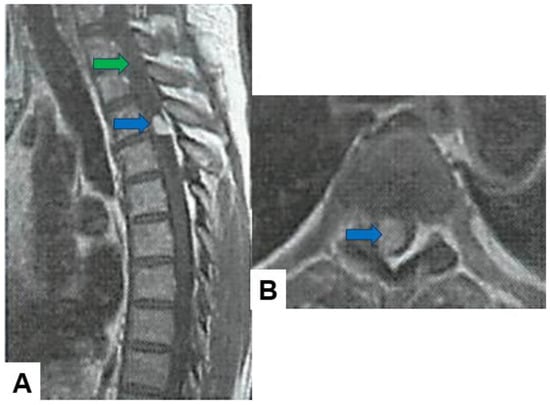

Hemangioblastoma: Hemangioblastomas usually appear as well-circumscribed intramedullary lesions with marked hypointensity in T1-weighted images and hyperintensity in T2-weighted images due to the presence of cystic components and vascularity. They typically demonstrate avid contrast enhancement (Figure 7).

Figure 7.

Fifty-four M, spinal hemangioblastoma, grade 1. (A) Enhanced T1-weighted midsagittal image; (B) enhanced T1-weighted axial image at T2/3. Blue arrows indicate tumor enhancement and green arrow shows syringomyelia.